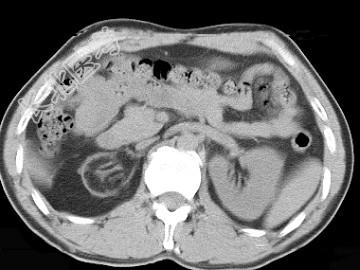

- 单项选择题男,18岁, 外伤后1小时,CT扫描如图, 最可能的诊断是 ( )

A、肾包膜下积液

B、肾脓肿

C、先天性肾萎缩

D、肾包膜下积血

E、肾挫裂伤